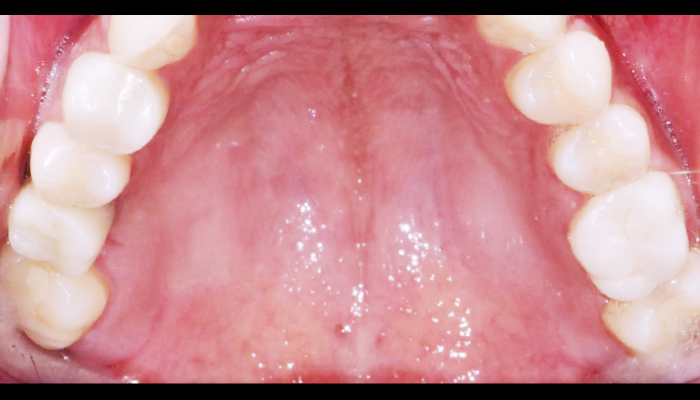

스케일링은 칫솔질로 제거되지 않은 치석과 치태를 제거하여 치석으로 인한 잇몸질환, 충치, 구취 등을 예방하는 치료입니다. 최근에 건강보험이 적용되어 1년에 한 번, 보험 혜택을 통해 스케일링을 받으실 수 있습니다.

스케일링 이런분께 추천드립니다!

다음과 같은 경우 스케일링 치료를 통해 건강한 치아로 회복하실 수 있습니다.